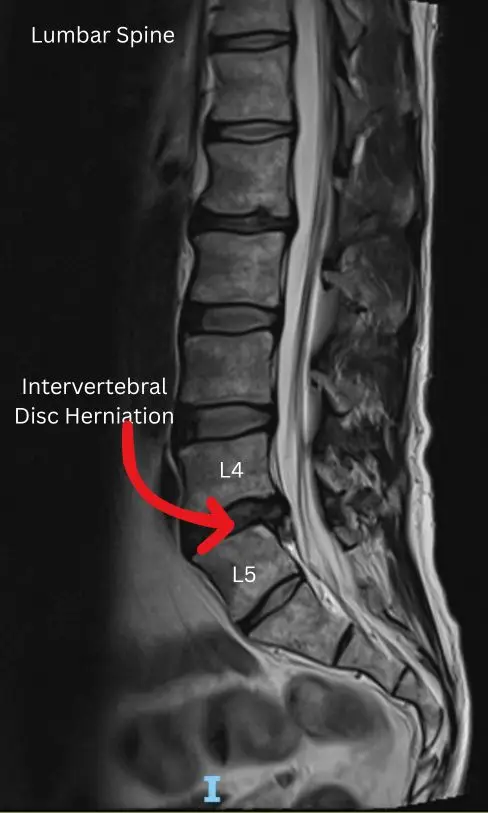

- MRI of the lumbar spine to confirm disc herniation

MRI remains the gold standard because it shows both the disc and the affected nerve root clearly.